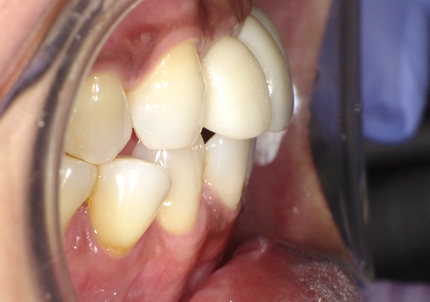

22.最終補綴物完成・装着口腔内写真(2021年1月)

23.自然な形態のインプラント歯頚部

適切な治療計画と治療技術を有することで、このような自然な形態のインプラント歯頚部を形成することができます。

24.口腔内写真

【 2018年 術前 】

【 2025年5月 現在 】